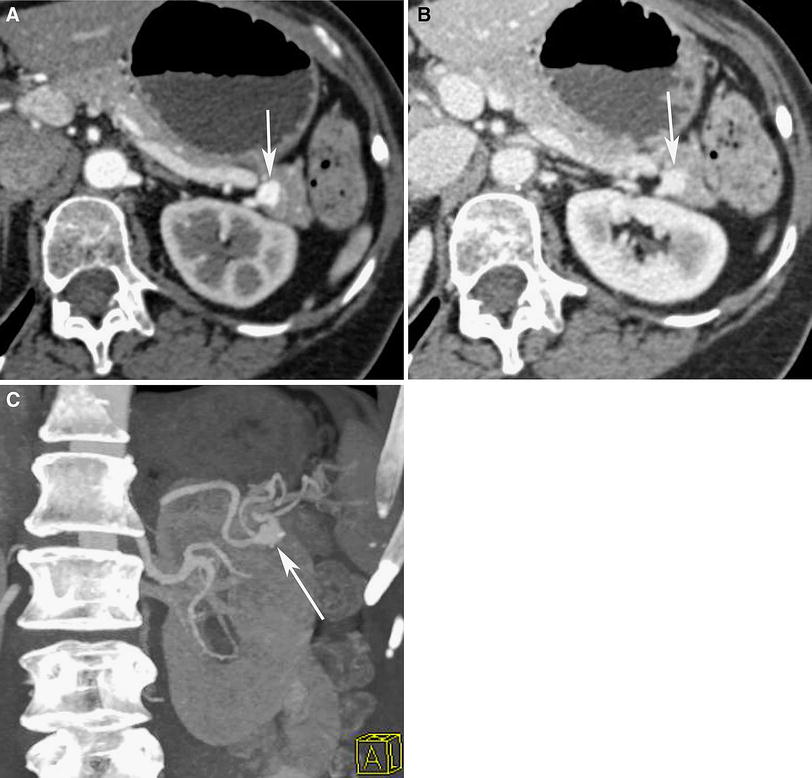

MediaObjects/261_2011_9830_Fig13_HTML.jpg

Fig. 13 67-Year-old woman imaged for evaluation of pancreatitis. A Arterial and B portal venous phase axial CT images show 1.0 cm vascular mass in the tail of the pancreas, which enhances similar degree to the abdominal aorta. C Oblique anterior MIP image confirms that this is 1 cm aneurysm arising from the splenic artery.